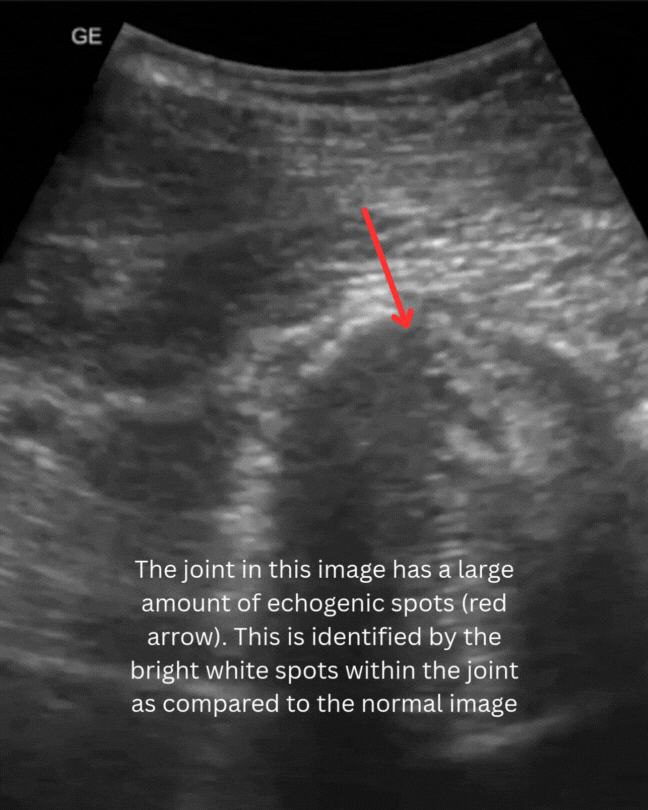

Ultrasonography is highly useful for evaluating the soft tissues of the joints. It allows for side-by-side comparisons, assesses joint fluid and surrounding structures, and facilitates targeted treatment through ultrasound-guided injections.